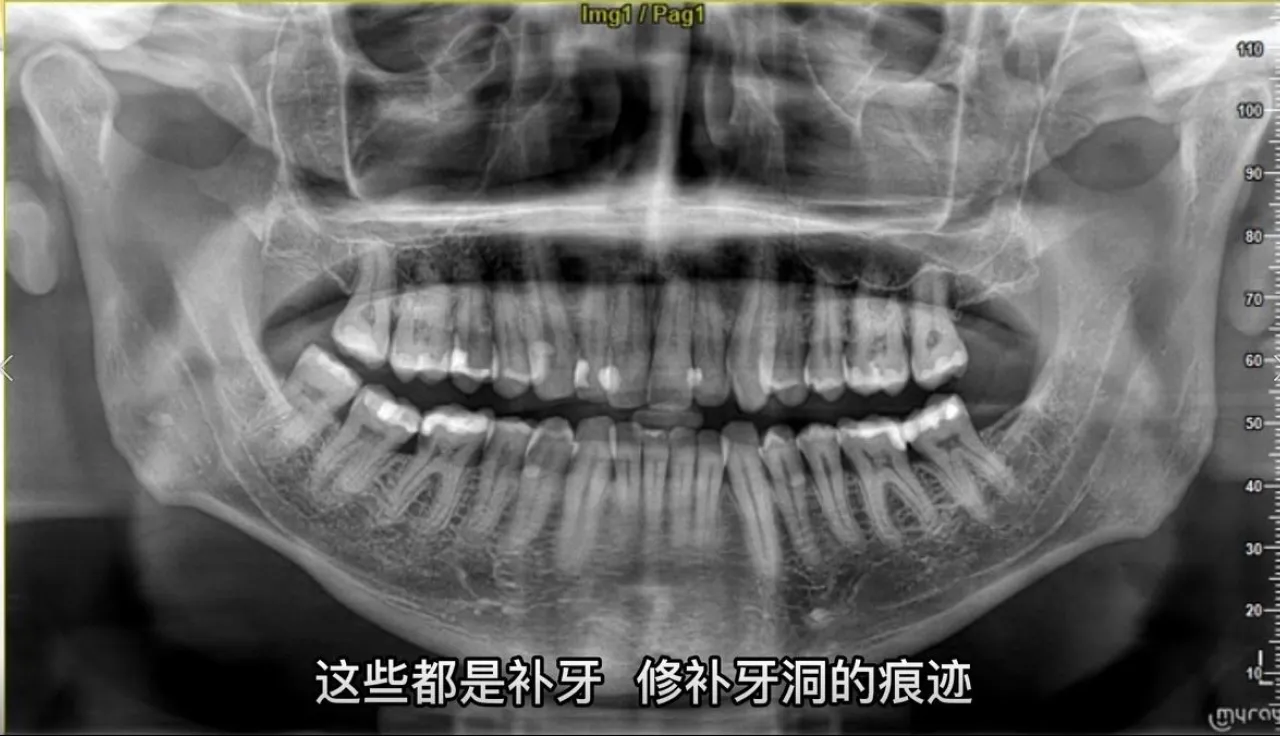

在本期视频中,康求恩医生将为我们讲解如何对冲突中的死者进行身份鉴定。你知道除了DNA之外,还有哪些证据有助于对死者进行身份鉴定吗?你知道美国女歌手麦当娜最有趣的体貌特征是什么吗?你知道绿眼睛的人占世界总人口的比例是多少吗?下面就请康求恩医生为我们逐一揭晓答案。